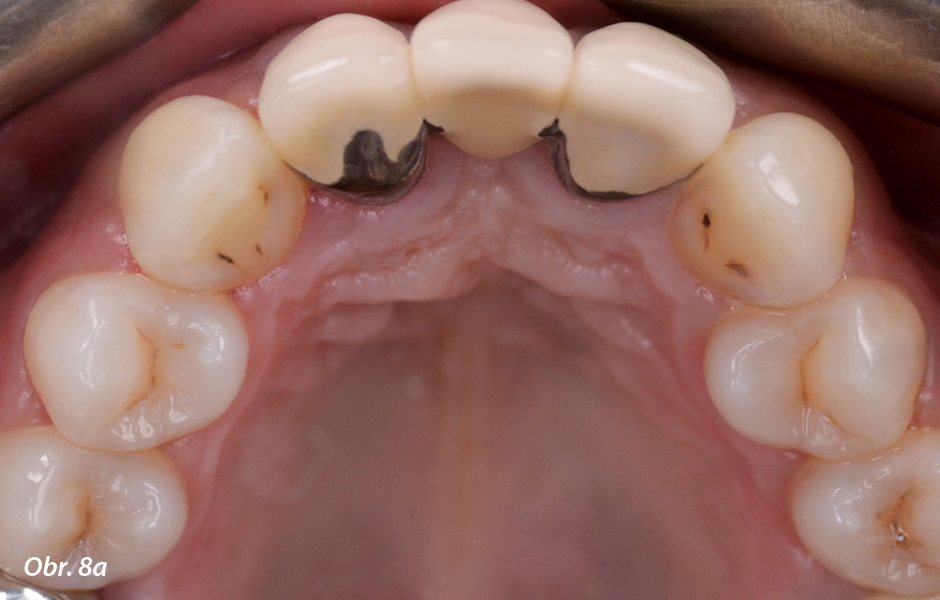

Druhá možnost ošetření vyhodnocená v podobě digitálního designu úsměvu posloužila jako základ pro přípravu wax-upu (obr. 6–8). Horní řezáky byly obroušeny a tvar obou špičáků a prvních premolárů byl upraven tak, aby bylo dosaženo symetrického vzhledu úsměvu a byl respektován optimální velikostní poměr mezi zuby. Vzhled rekonstrukce byl vyhodnocen společně s pacientkou na intraorálním mock-upu (obr. 9–11).